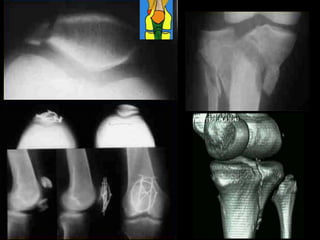

ANATOMIA DO JOELHO

Patela

Fossa

intercondilar

Epicôndilo

lateral

medial

Tubérculo

Face art.

TÍBIA

FÍBULA